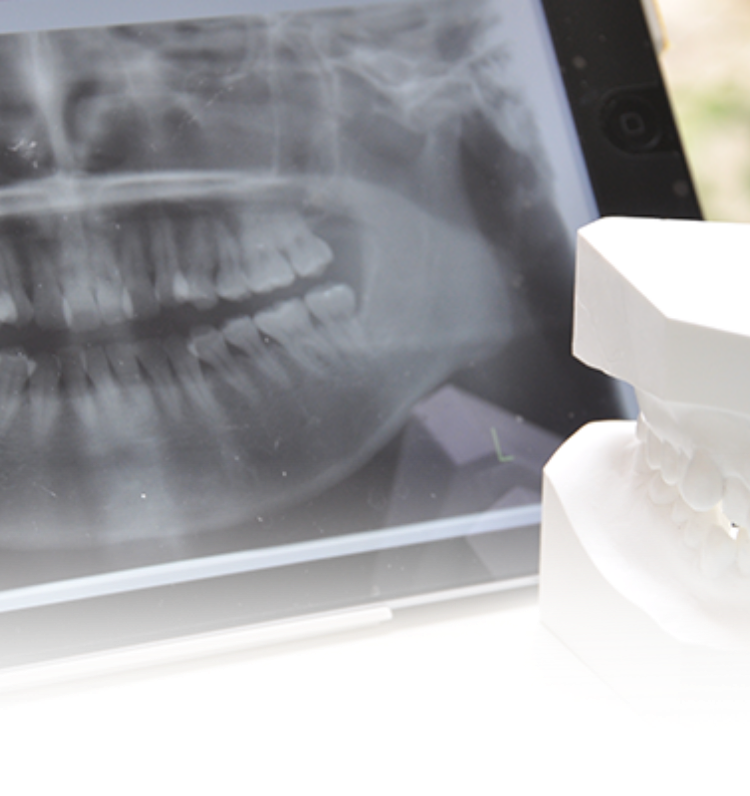

• Comprehensive Diagnosis全顎治療における診査診断最適な治療をご提案